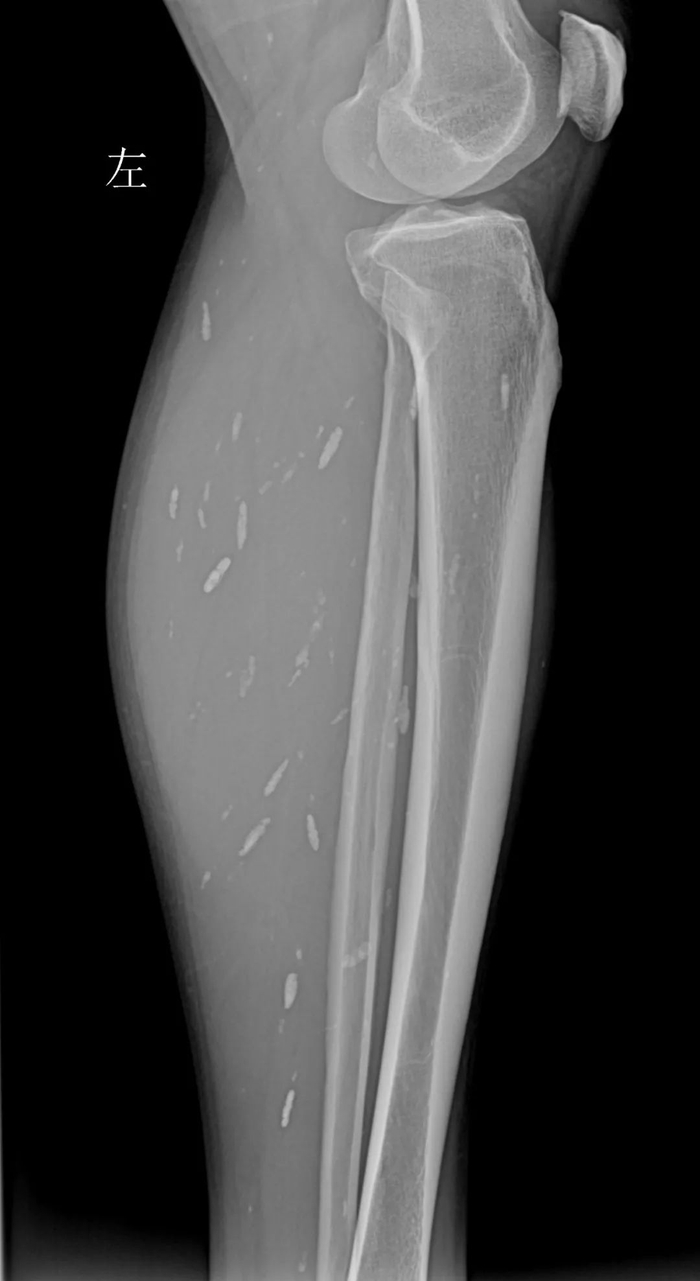

令人吃惊的是,除了头部,影像检查还提示,患者双下肢也有囊虫,分散密布在左小腿和右小腿处。

(左小腿X光片,见肌肉内多发囊虫病灶。)